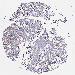

CANCER BREAST CANCER Show tissue menu

BRCA TCGA BRCA VALIDATION PROTEIN EXPRESSION

ANTIBODIES

AND

VALIDATION